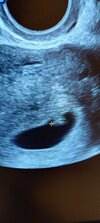

Witam sie skromnie. 😊 Mam nadzieję że zostanę tu do końca . Do porodu. Ostatnio to życie idzie mi pod górkę miałam dwa poronienie , ostatnie we wrześniu br i bum w grudniu tescik pozytywny. Szok . Moje przerażenie że jak to ? Tak szybko ? Znowu strach ... Zrobiłam betę jedna potem druga piękny przyrost bo ponad 100% progesteron też piękny. Oczywiście moja radość zmalala jak zauważyłam krew... Niewielka ... Ale była .wizyta u lekarza nic nie widzi niepokojącego . Wzięłam odrazu progesteron besisn i luteinke dopochwowo .. i tak chodziłam chodziłam do wizyty które sie odbyła wczoraj 😊😊😊 termin 10.08.2024

Jestem obecnie 6t6dz😊😊😊 mam ogromną nadzieję że zostanie z nami do końca i będę tulić maleństwo w sierpniu 🥰

• IMG_20231221_084355166_HDR.jpg

IMG_20231221_084355166_HDR.jpg

2 MB · Wyświetleń: 111

Ja po wizycie. Ciążowy jest, żółtkowy jest, zarys zarodka też, ale tętna jeszcze nie widać. Gin powiedziała, że za słaby sprzęt ma do oceny. Wychodzi mi 6+0, ewentualnie 5+6. Powiedziała, że raczej 5+6. Torbiel mi urosła centymetr od zeszłego tygodnia i stąd moje bóle. Po porannym plamieniu śladu już nie ma, powiedziała, że szyjka czysta, więc musiało to być coś z pochwy. Założyła mi kartę ciąży i zleciła komplet badań, ale to na spokojnie zrobię pod koniec roku.